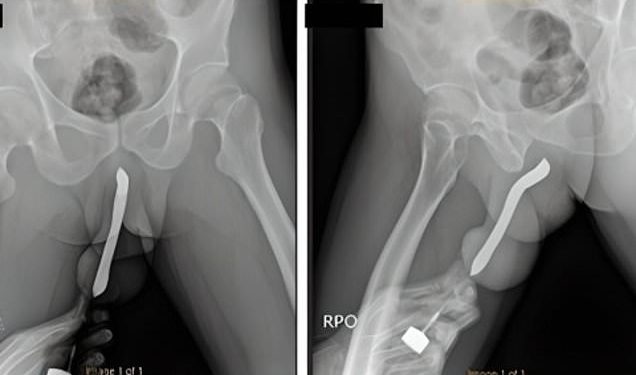

A man was left in excruciating pain after a toothbrush he shoved into his penis snapped during sex.

According to Doctors, the 43-year-old waited 12 hours before seeking medical attention for his eye-watering injury.

Asked why he had a toothbrush in his penis, the unnamed Indonesian man confessed to performing DIY surgery for his ‘sexual satisfaction’.

Medics were told he first made a ‘small incision’ to insert toothbrushes in 2017.

Sharing details of the incident, doctors from the Soetomo General Academic Hospital in East Java told how the man required a two-hour op to repair his fractured penis.”

They wrote in the International Journal of Surgery Case Reports: ‘The patient sustained a penile injury during sexual intercourse in the woman-on-top position the night before.’

He had an ‘eggplant deformity,’ a tell-tale sign of penile fracture.

Medics said the man was discharged three days after surgery, reporting no issues.

He returned for a follow-up appointment one month later, where he was able to pass urine and claimed not to have any complications.

The ‘deformity’ had also vanished